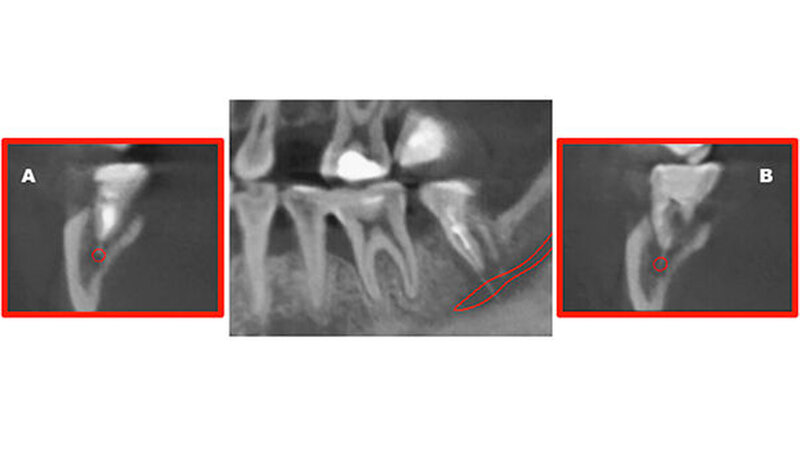

Der Zahn 47 stellte sich parodontal geschädigt und 1-gradig gelockert dar. Das Orthopantomogramm (OPTG) und der anschließend angefertigte Zahnfilm (Abbildungen 2 und 3) zeigten am Zahn 47 apikal weit überextrudiertes Wurzelfüllmaterial. Die Patientin wurde aufgrund der klinischen und der röntgenologischen Befunde sofort an die Klinik und Poliklinik für Mund-, Kiefer- und Gesichtschirurgie überwiesen.

Die dreidimensionale Darstellung des Unterkiefers rechts mittels digitaler Volumentomografie (DVT, Abbildung 4) vervollständigte den Nachweis von röntgenopakem Material im Bereich der Wurzelspitzen des Zahnes 47 mit direktem Kontakt zum Nervus alveolaris inferior. Die Rücksprache mit dem ausländischen Behandler ergab die Information, dass es sich bei dem Füllmaterial um Guttapercha zusammen mit einem paraformaldehydhaltigen Zement handelte.